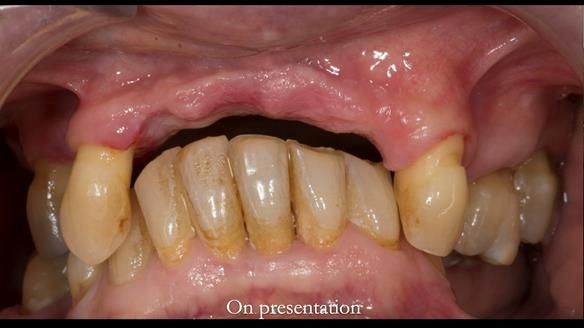

In this edition, I present the removable partial denture treatment for Jean, an 80-year-old woman with a sore mouth caused by a soft tissue-supported 'gum stripper' acrylic denture and a clenching habit. Below, I outline the step-by-step process of her treatment. It wasn't straightforward; I had to remake the denture after it fractured to achieve a satisfactory result. Each patient is unique, and sometimes a new RPD serves as a prototype. Occasionally, I need to make adjustments, learn from any mistakes, and refine the design to get it right.

The treatment has been a success over the past 4 years.